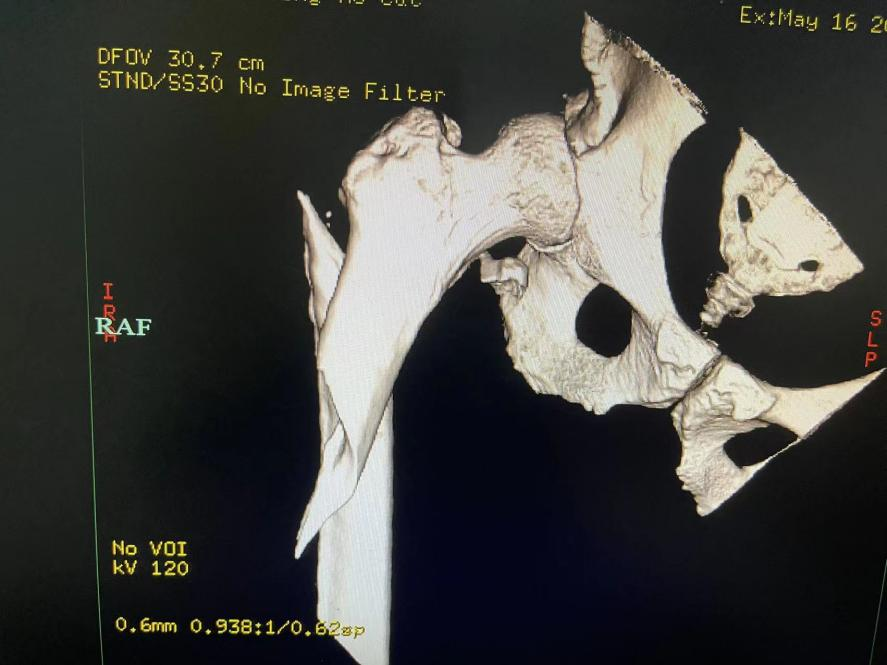

病例介紹 居住在椒江區(qū)的陳大爺70多歲了,患有帕金森綜合征20多年,慢性肺部感染約10年。一年前,陳大爺不慎跌倒導致右股骨粉碎性骨折,入住臺州市中醫(yī)院骨傷科。 病案分析 接診醫(yī)生我院骨傷科副主任中醫(yī)師徐榮敏認為,此類股骨上端骨折的病人最好的治療方案是手術。 如果保守治療,眾多并發(fā)癥是導致患者近期死亡的主要因素,雖然骨科手術并不是太難,但是患者平時2至4小時就需要服用抗帕金森藥物和吸痰,平時主要靠兒子照顧,藥效一過,痰就咳不出,全身抖動厲害。麻醉、手術、護理也各有難度,疊加起來就是難上加難,手術風險較大。 選擇手術還是保守治療,需要患者及其家屬做出選擇。 抉擇過程 在得知手術風險時,患者及其家屬也有過遲疑,考慮是否轉上級醫(yī)院治療。 但李大爺慶幸了自己的第一次抉擇,李大爺說自己幾年前在別家醫(yī)院ICU宣告治療無效回家后,后來到臺州市中醫(yī)院呼吸科才治療好的! 這次面臨著第二次抉擇,大爺還是相信臺州市中醫(yī)院!選擇手術! 手術經過 經過呼吸科、神經內科、心內科、手術室、麻醉科、ICU等科室的聯(lián)合會診,骨傷科徐榮敏醫(yī)師、陳國軍醫(yī)師等制定了詳細的手術計劃,麻醉科主任聶運明、麻醉醫(yī)生王曉等在術前也制定了詳細的麻醉計劃和應急準備,包括麻醉藥物控制劑量、術中鼻飼給予抗帕金森綜合征的藥物等。 幸運地是,手術在2小時之內順利完成,術后ICU密切觀察,第二天即回骨傷科病房。 術后護理 在常規(guī)中西醫(yī)結合治療的同時,護士長蘇韓、責任護士錢淼淼等護理同仁為其制定了細致周詳的護理計劃。在拍背、吸痰、功能鍛練等常規(guī)護理基礎上,運用辨證施護原則,因人因病而異,綜合運用耳穴埋豆、腕踝針、穴位貼敷、隔物灸等中醫(yī)適宜技術,避免了壓力性損傷、下肢深靜脈血栓、肺栓塞等并發(fā)癥的發(fā)生,安全的度過了圍手術期。 幾天后考慮患者平時患有慢性肺部感染,予轉入呼吸科。經過約1月的治療護理,李大爺恢復良好后出院! 一年后大爺的骨折愈合良好。 據徐榮敏醫(yī)師介紹,在骨傷科像這樣的老年病人其實有很多,患者往往有高血壓、糖尿病、冠心病、腦梗死、帕金森綜合征、慢性阻塞性肺疾病、腎功能不全等基礎疾病。骨傷科作為浙江省“十三五”中醫(yī)藥重點學科,設有重點學科研究室,對治療老年骨傷科疾病有獨特的研究和良好的效果。 脊柱創(chuàng)傷骨傷科為浙江省中醫(yī)重點??啤⑴_州市重點學科、上海中醫(yī)藥大學“石筱山傷科”聯(lián)盟單位。 學科特色:繼承傳統(tǒng)中醫(yī)骨傷特色治療理念,與時俱進,不斷吸收國內外當代先進骨科治療技術,中西醫(yī)結合,注重微創(chuàng),安全有效,精心護理,快速康復。 診療專長:四肢骨折脫位的手法復位加夾板(石膏)固定或手術治療;脊柱骨折的切開復位內固定;骨質疏松癥、風濕骨病、脊柱腰腿痛、骨關節(jié)炎的中西醫(yī)結合特色治療;軟組織疾患的針刀和體外沖擊波治療,骨質疏松性脊柱骨折的骨水泥成形術;頸腰椎間盤突出癥、椎管狹窄癥的椎間孔鏡手術和椎間融合手術,肩髖膝人工關節(jié)置換術,肩膝關節(jié)疾病的關節(jié)鏡手術,穴位貼敷等中醫(yī)特色治療護理技術,老年病人術后快速康復。 人才隊伍 :高級職稱5人,碩士研究生4人,多人擔任國家與省市級學會委員、副主委,主持市廳級課題多項,撰寫論文幾十篇,學術專著多部。 科室理念:中西結合,發(fā)揮特色,無痛少痛,快速康復。 聯(lián)系電話:0576-88825725